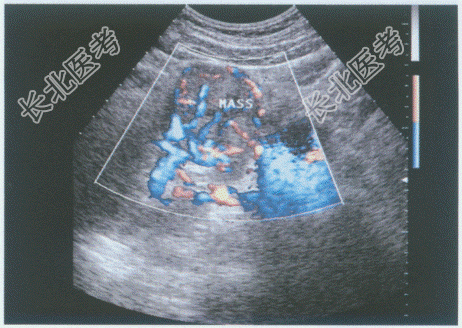

超声综合描述: 右肾失常态,下极可见6.7cm×6.5cm中等回声(图1), 边界尚清晰,内回声欠均匀, 向外突起,CDFI: 内部及周边可见丰富动、静脉血流信号。见彩图。

右肾静脉、下腔静脉肝后段管腔增宽,内可见中等回声(图2、图3), CDFI:该段内血流信号充盈缺损。